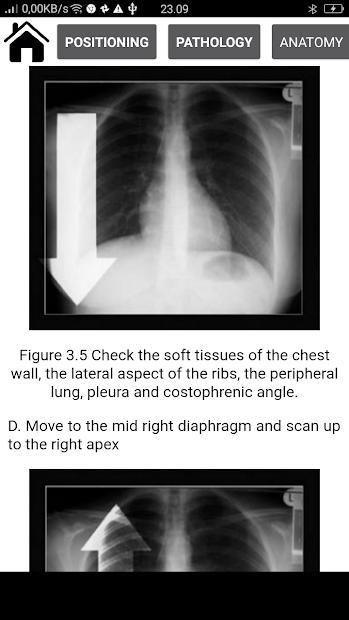

> Review areas